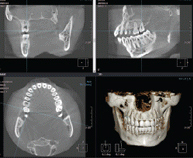

시작부터 다르다!

3차원 정밀진단 시스템

얼굴 골격을 빠짐없이 분석합니다

얼굴 골격의 모든 방향을 빠짐없이 촬영하고

치아와 치조골의 상태 및 잇몸뼈의 양과 길이 등의

전반적인 상태를 정확하게 측정하고 진단하여

한치의 오차 없는 시술로 진료의 안정성을 높힙니다.